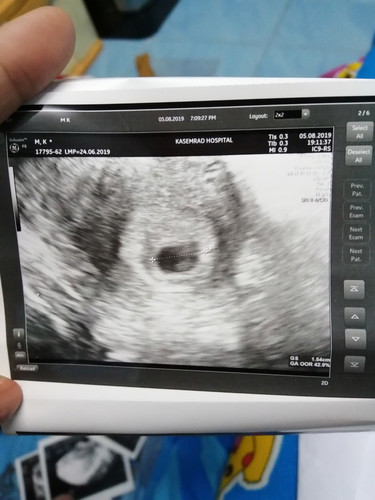

ตั้งครรภ์6วีค ผลซาวด์เจอหัวใจเด็ก และเจอถุงขนาด1.57ซม.เล็กไปไหมคะ คุณแม่6วีมีขนาดเท่าไหร่บ้าง หมอก็ไม่ได้บอกอะไร